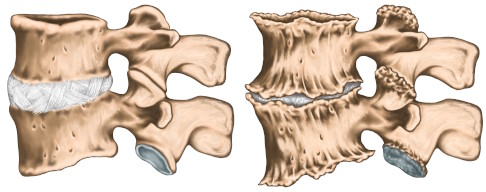

Durch die degenerativen Prozesse wird der betroffene Bereich der Wirbelsäule immer instabiler. Der Körper versucht, die Instabilität mit zusätzlichem Knochenwachstum auszugleichen – er bildet Knochenwucherungen und Knochensporne (Spondylophyten) aus. Passiert das im hinteren Bereich der Wirbelkörper, spricht man von einer Retrospondylose.

Außerdem können die Spondylophyten zweier Wirbelkörper miteinander verwachsen und dadurch Wirbelkörper knöchern verbinden. Diesen Vorgang nennt man Ankylose. Dadurch versteift die Wirbelsäule und es drohen Bewegungseinschränkungen.

- Spondylosis deformans oder Ankylose: Versteifung der Wirbelsäule aufgrund von Verwachsungen der Spondylophyten mit Rückenschmerzen und Einschränkung der Wirbelsäulenbeweglichkeit.